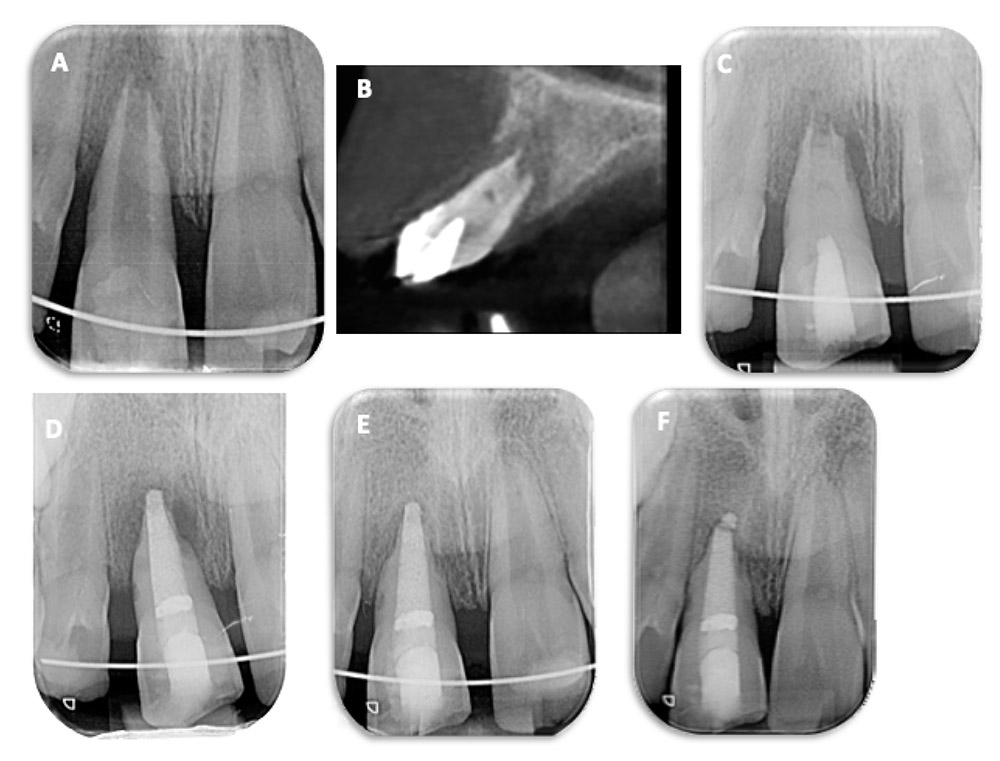

درمان عصبکشی (Root Canal Therapy)

اصلیترین درمان در تحلیل التهابی ریشه است. مراحل شامل:

- برداشت پالپ نکروزه و بافت عفونی

- پاکسازی کامل کانالها با مواد ضدعفونیکننده (مانند هیپوکلریت سدیم)

- استفاده از داروهای داخل کانالی مانند کلسیم هیدروکسید برای مهار فعالیت سلولهای تحلیلگر

- پر کردن کانال با گوتاپرکا و سیلر مناسب

کلسیم هیدروکسید نقش کلیدی در توقف تحلیل و تحریک ترمیم بافتی دارد.

- رادیوگرافی دندان (X-ray): نشاندهنده نواحی تحلیل در اطراف ریشه

- CBCT (Cone Beam CT): تصویربرداری سه بعدی دقیق برای بررسی میزان و محل تحلیل